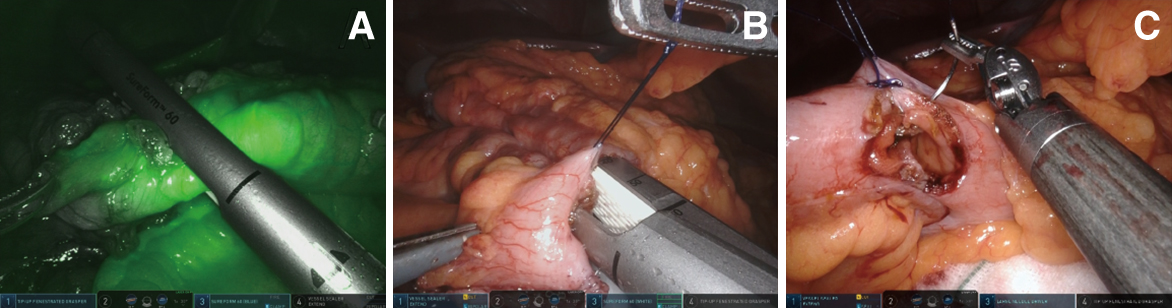

肝彎曲から盲腸まで外側授動を追加し,内側アプローチの層と連続させることで,盲腸から横行結腸まで完全に授動した.回腸はバウヒン弁より口側約10 cmで,結腸は横行結腸やや肝彎寄りで切離することとした.郭清端より腸管切離予定ラインに向かって腸間膜を処理し,切離予定ラインで腸管を全周に露出した.Firefly®機能を使用してICG蛍光法による血流評価を行い,腸管切離ラインを最終的に規定した.血流が良好であり,吻合にあたって十分な可動性を確保した位置で腸管切離を行った結果,肛門側切離ラインは10 cmよりやや肛門側となった(Fig. 3A).結腸切離はSure Form® 60 mm Blueを使用し回腸切離は同Whiteを使用した.

Anastomosis in Case 1. A: Before using SureForm® 60 mm to dissect the intestine, vascularity of the cut end was confirmed with ICG angiography. B: Enterocolostomy using SureForm® white 60 mm by overlap method was performed. C: The entry hole was closed by manual suture with 3-0 STRATAFIX®.

回腸横行結腸吻合をoverlapで行った.縫合器挿入口近傍に支持糸をかけ,Sure Form®を挿入し側々吻合を行った(Fig. 3B).共通口は3-0 STRATAFIX®で連続縫合し閉鎖した(Fig. 3C).